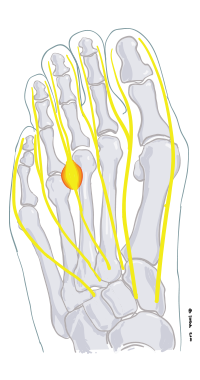

Mortons neurinom

En liten förtjockning bildas i korsningen mellan två tånerver. Oftast mellan tredje och fjärde tån.

Förtjockningen, och därmed nerverna, kommer i kläm mellan framfotens ben då man går.

Fenomenet ger upphov till smärtor, stickningar och känselbortfall i framfoten och engagerade tår.

Behandlingen brukar inledas med pelottinlägg.

Nästa alternativ är operation där man kirurgiskt avlägsnar förändringen.